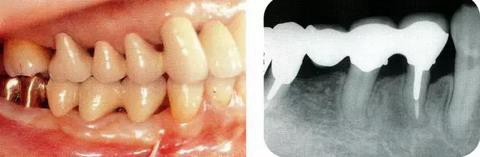

360截圖20170120113944118.jpg

圖17-3   拔牙的同時(shí)做骨外科處理,讓殘留的骨可以盡量平坦化。為了獲得頰側(cè)的附著齦,采用了游離齦瓣的處理。

360截圖20170120113954454.jpg

圖17-4(左),5 (右)  術(shù)后9年的口腔內(nèi)照片和X線片,牙槽嵴平坦化,牙周探診數(shù)值很小。